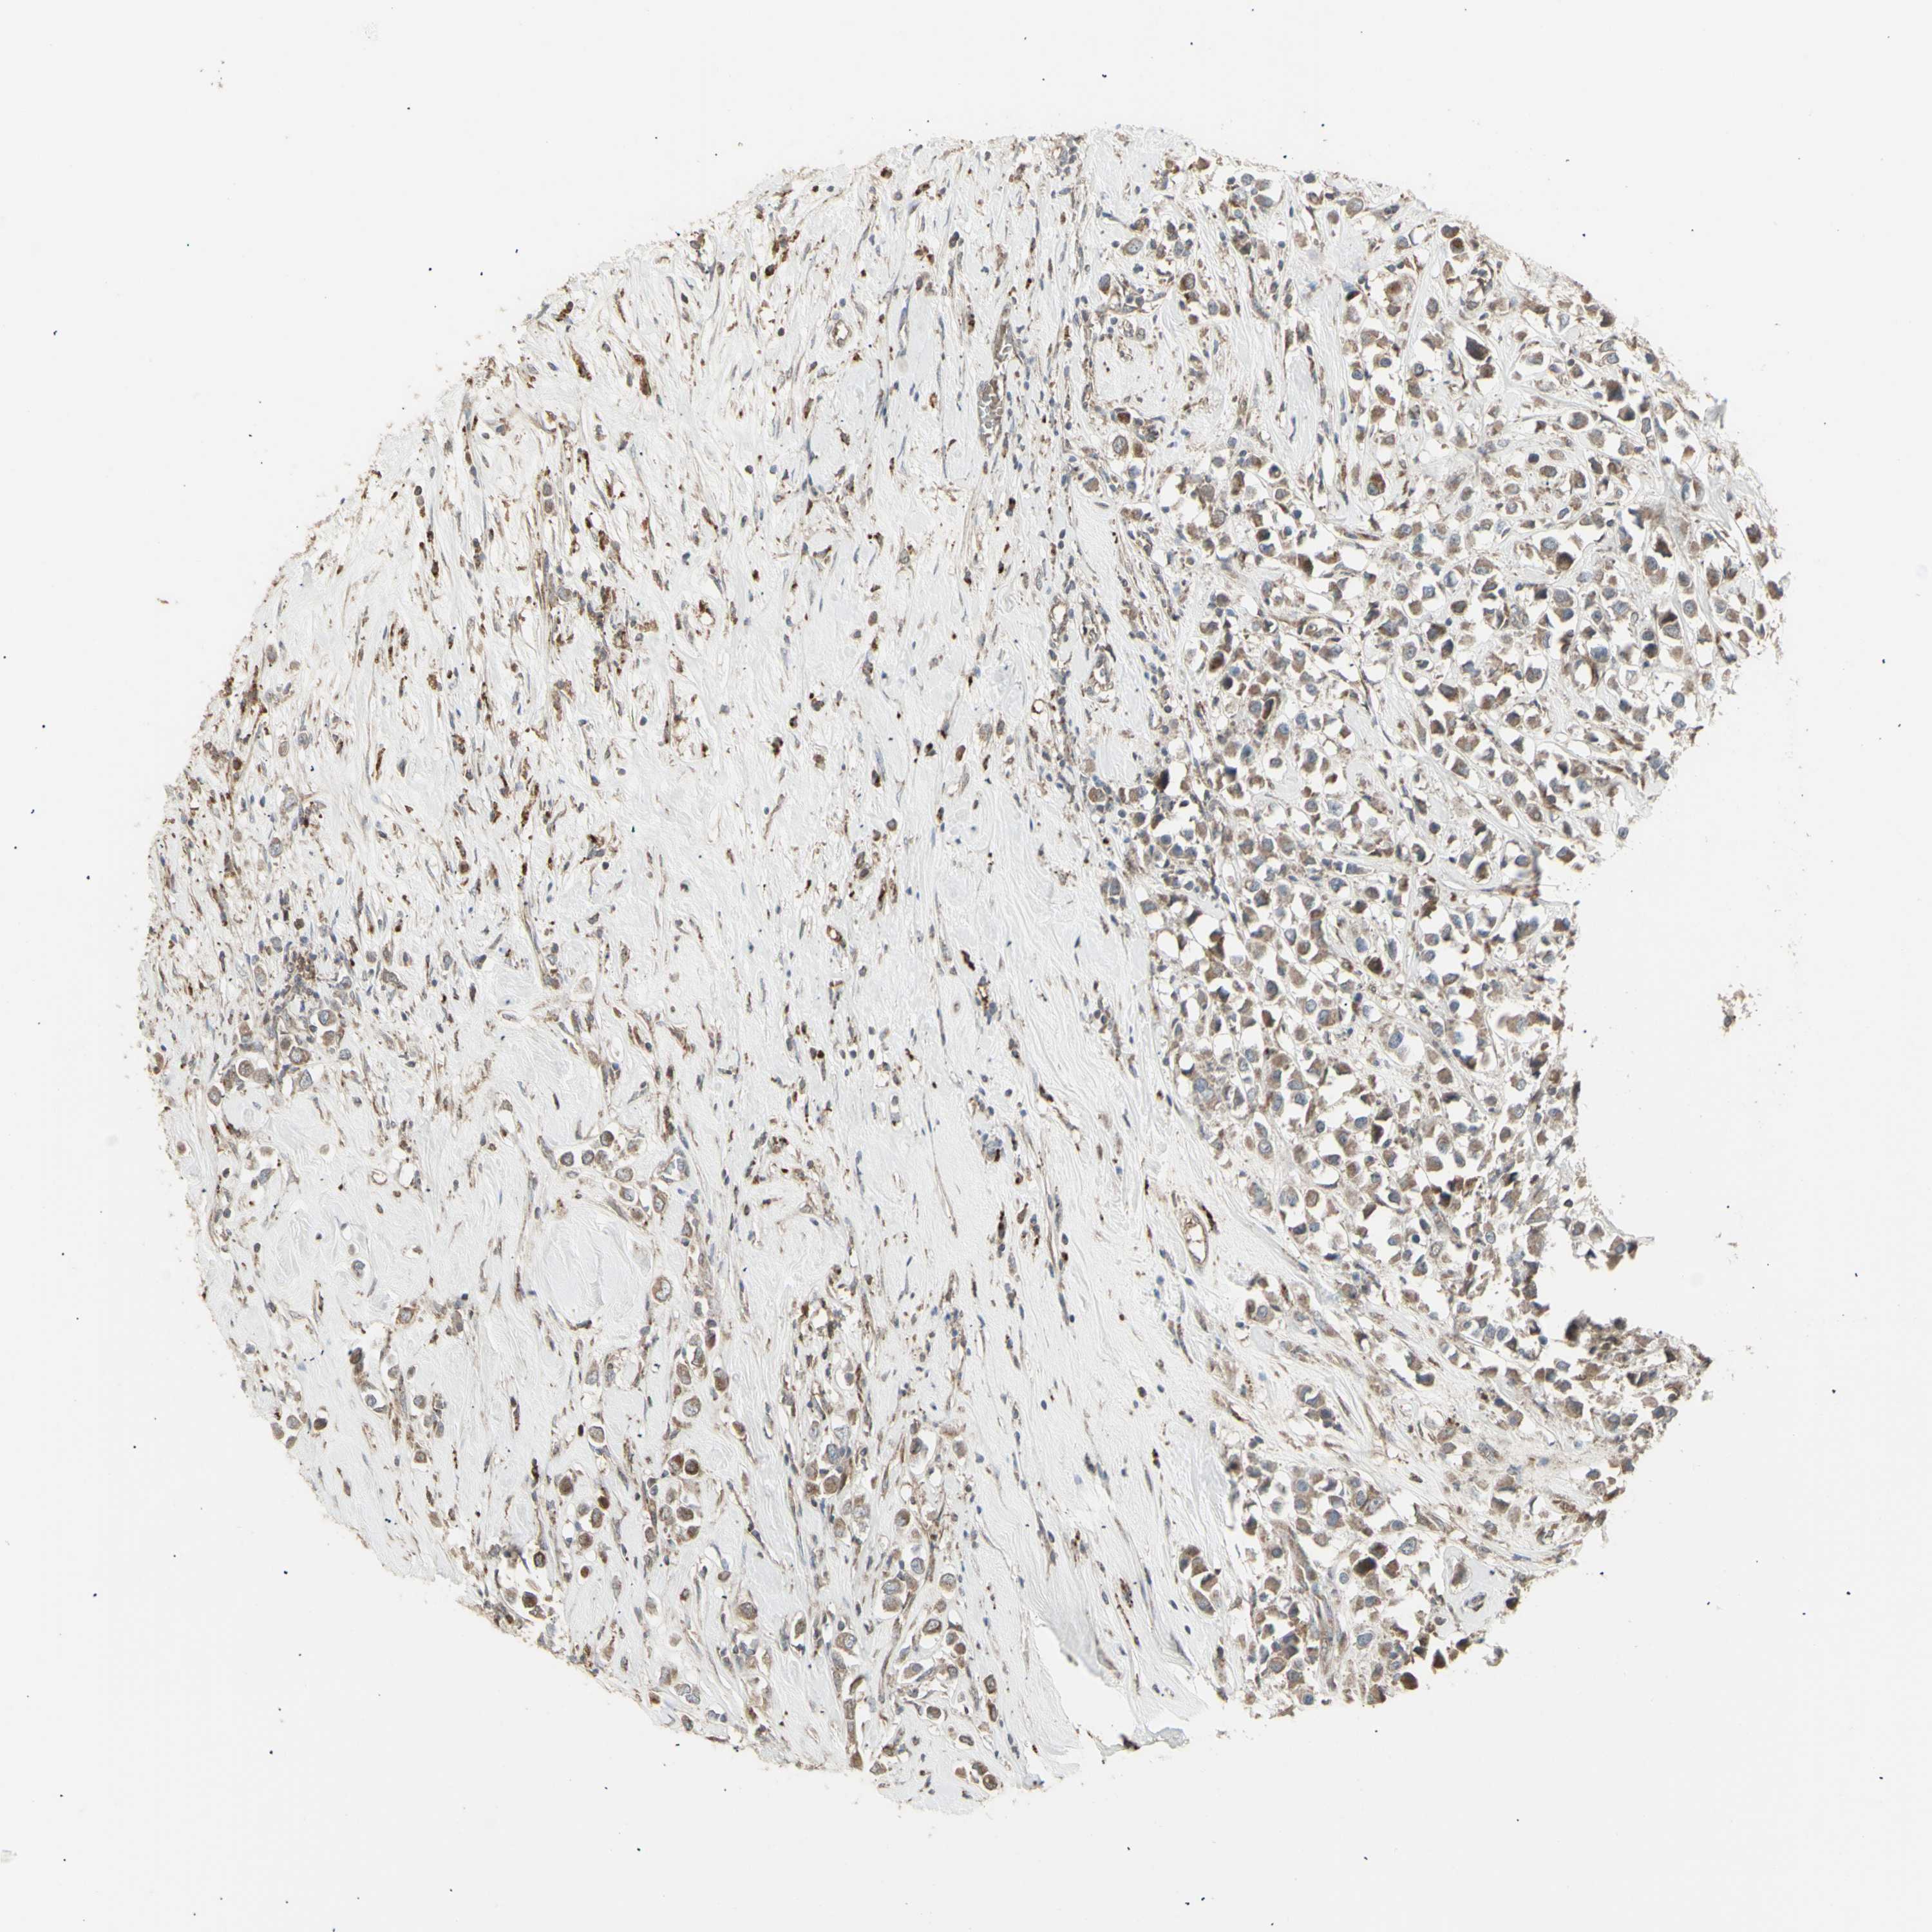

BRCA TCGA BRCA VALIDATION PROTEIN EXPRESSION

ANTIBODIES

AND

VALIDATION